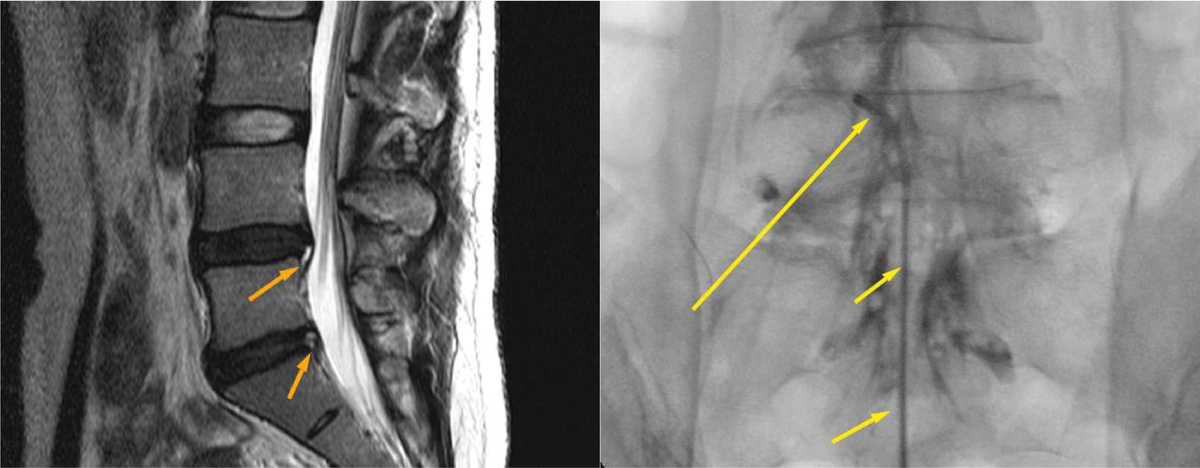

진단은 병력과 이학적 검사로 시작한다. X-ray는 뼈 정렬과 불안정성을, CT는 미세 골절이나 후관절 상태를 확인한다. MRI는 추간판·신경 압박을 가장 정확히 보여준다.

신경차단술은 C-arm으로 병변을 보며 약물을 주입해 염증과 부종을 가라앉히고, 신경성형술은 특수 카테터로 유착을 풀어 통증을 완화한다. 두 시술 모두 전신마취가 필요 없고 회복이 빠르다. 시술 후에는 자세·호흡·코어 재교육을 병행해야 재발을 줄일 수 있다.